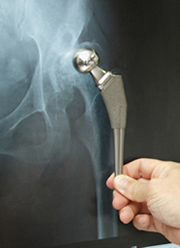

人工股関節の一例